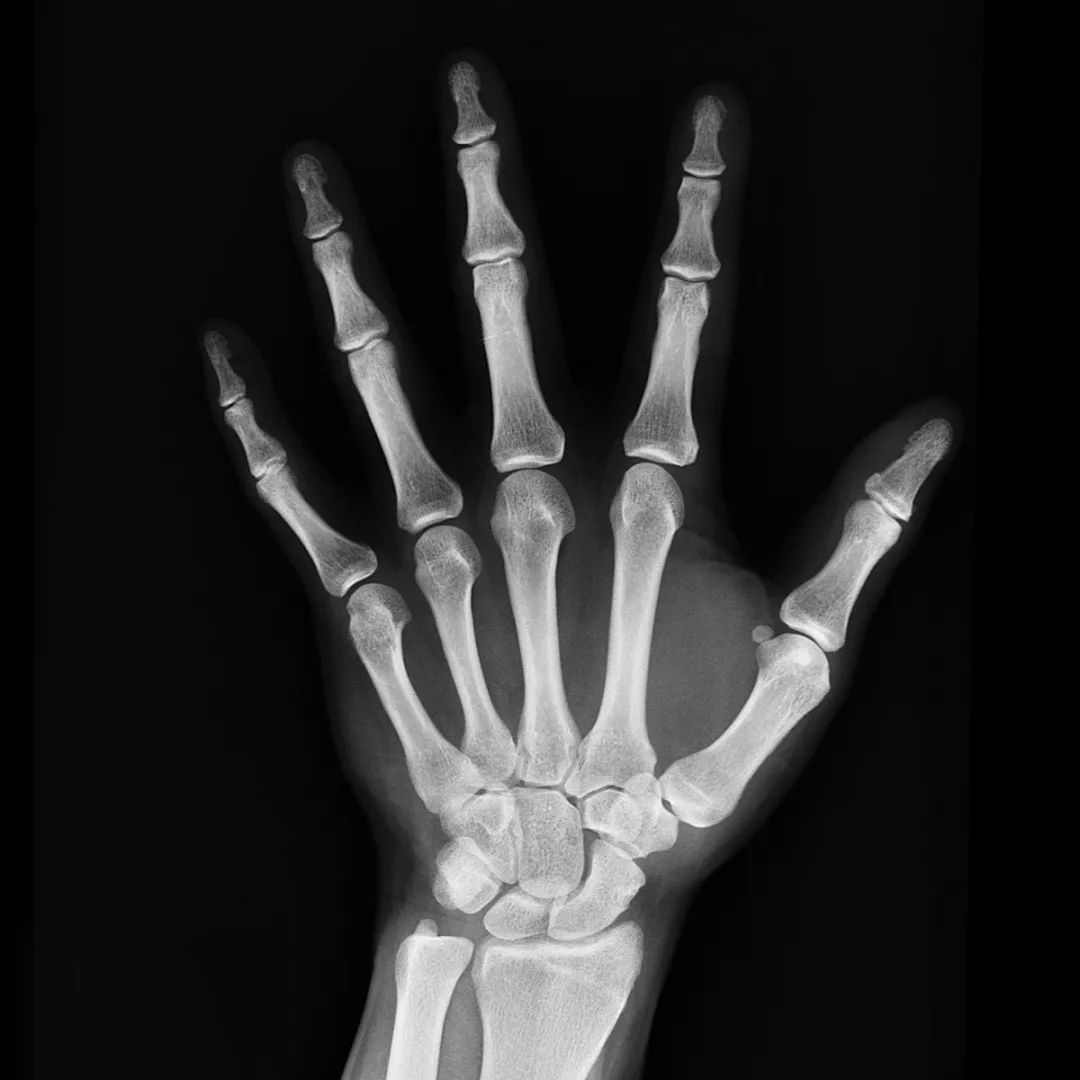

X线造影剂密度会高于或低于人体软组织,因此在X线照射下,其显影密度与周围组织形成明显的差异,由此可观察人体器官形态和功能是否正常。

硫酸钡造影剂属于固体造影剂,也是阳性造影剂,在X片上呈白色。

因具有吸收X线的能力,除了用作造影剂,硫酸钡还可用于制造防X射线辐射材料、根管糊剂等。